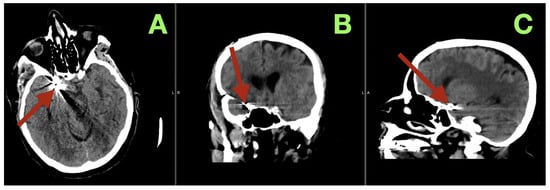

During the vasospasm-risk period, serial transcranial Doppler studies of the patient’s right middle cerebral artery (MCA) velocities ranged from 85 to 105 cm/s, and her fetal PCA (fPCA) velocities ranged from 55 to 70 cm/s, indicating that there was no clinically relevant vasospasm detected sonographically. On the fifth postoperative day, non-contrast CT (Figure 3) imaging confirmed the stable position of the clip, no interval hemorrhage, no territorial hypodensities, no interval change in the configuration of the ventricles, and no interval hydrocephalus. Additionally, the basal cisterns remained open, and the basal ganglia were normal in appearance.

Figure 3.

Postoperative day 5 non-contrast CT. (A) Axial section at the level of the skull base demonstrates the aneurysm clip at the right carotid–posterior communicating region (arrow), with expected localized metallic artifact and no evidence of recurrent subarachnoid hemorrhage, new intraparenchymal bleeding, or territorial hypodensity. The surrounding basal cisterns at this level remain discernible, without mass effect. (B) Coronal reconstruction confirms stable clip position within the right parasellar and suprasellar corridor (arrow), with preserved ventricular configuration and no radiographic signs of acute hydrocephalus or midline shift. (C) Sagittal reconstruction localizes the clip construct along the intended carotid–posterior communicating junctional plane (arrow), demonstrating anatomical coherence of the skull-base region and absence of secondary compressive changes.